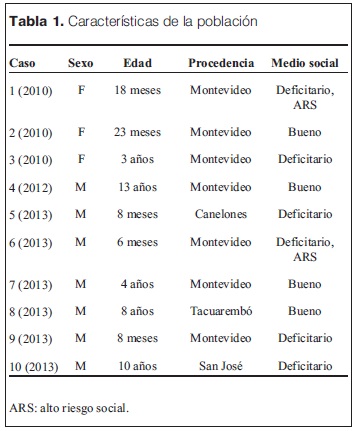

Como se observa en la tabla 1, en los cuatro años analizados hubo diez casos, de los cuales seis en el último año; con edades comprendidas entre seis meses y trece años y de ellos siete fueron varones. Nueve niños provenían de Montevideo y área metropolitana.

Solo cuatro de los niños pertenecían a un medio social aceptable, habiendo en el grupo mayoritario dos casos de alto riesgo social (consumo problemático de sustancias y residencia en institución pública).

En cuanto a las características del evento (tabla 2) en siete de los casos el material aspirado fue de sustancias orgánicas (carne, uvas, lentejas, semillas, cartílago), que ocurrió durante la alimentación (almuerzo, cena).

En tres ocasiones fue de material no orgánico (comprimido, tapa de bolígrafo, sujetador metálico), uno solo de ellos radioopaco.

En los casos en los que el episodio de sofocación fue presenciado por un adulto, se generó una consulta dentro de las primeras 24 horas. En el caso en que no estuvo presente (caso 5), la consulta se produjo después del tercer día.

Nueve niños estaban en su hogar de alojamiedeleonardisdaniel@gmail.comnto, y uno en la escuela.

La primera asistencia fue en hospital de adultos (caso 1), policlínica (casos 2, 3 y 9), hospital regional (casos 5, 8 y 10), emergencia móvil (casos 6 y 7) y en HP (caso 4).